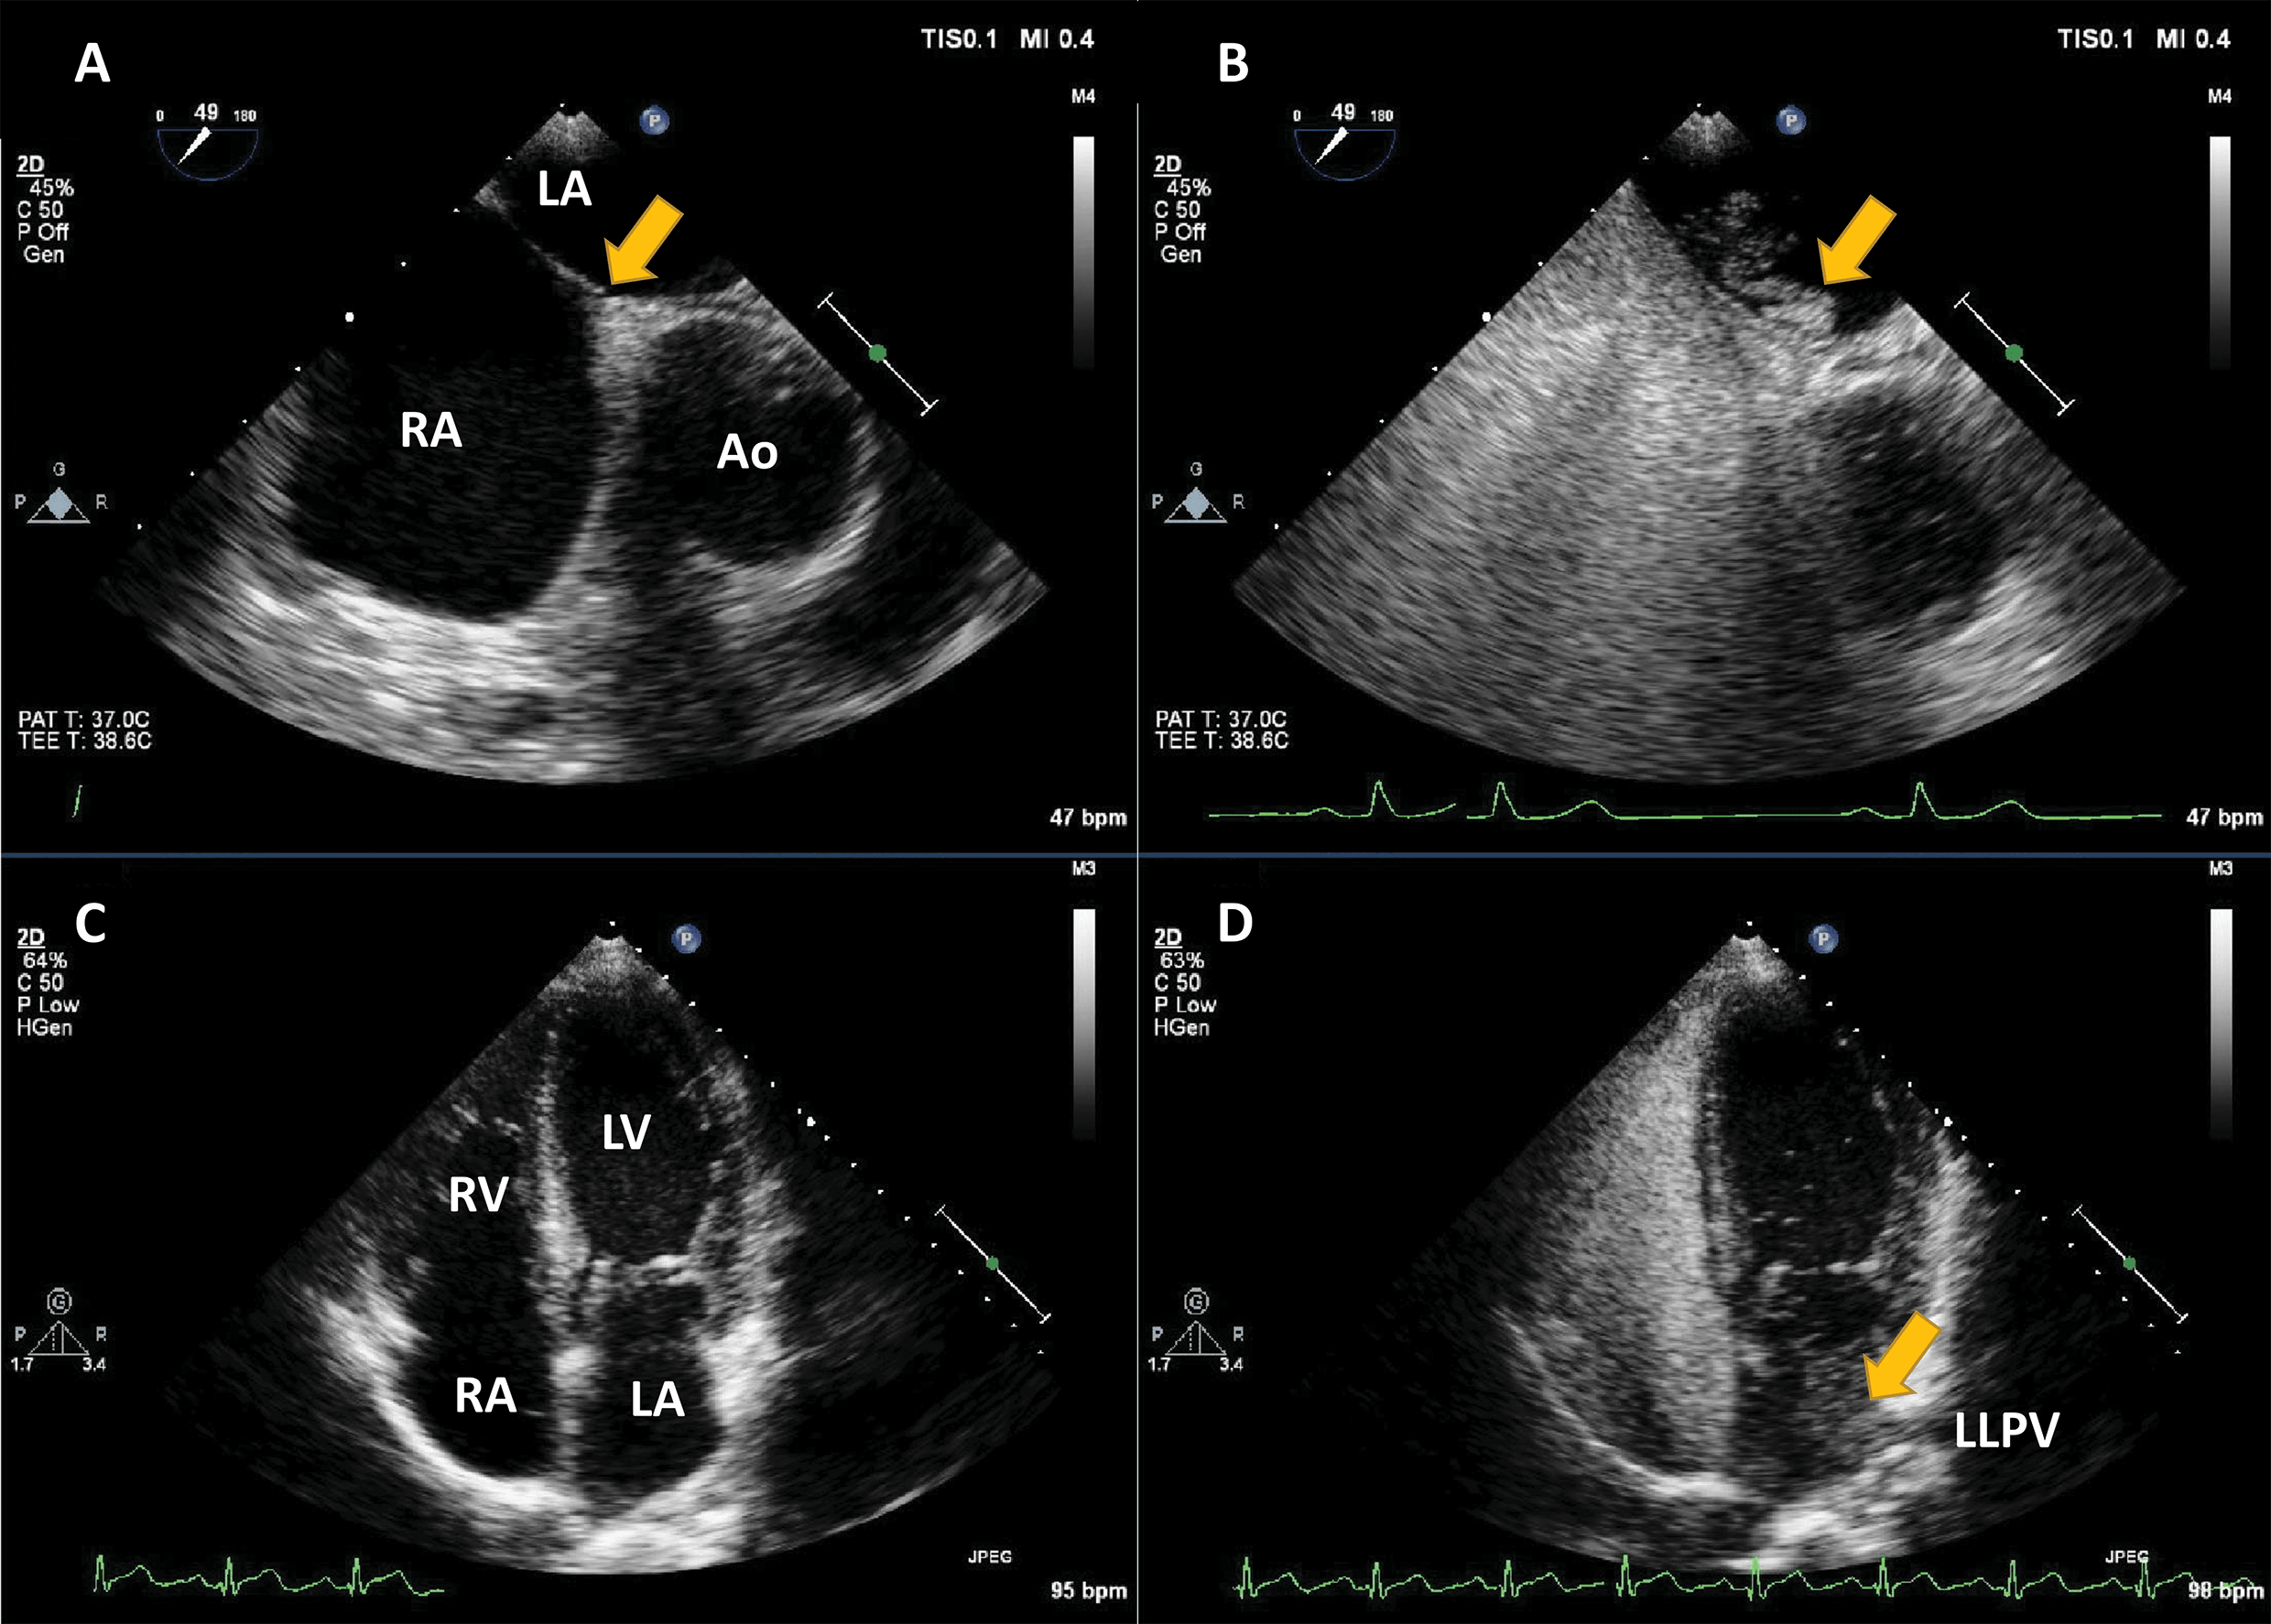

which has been used for the selective detection of right-to-left shunting (Fig. 1, Video 1) [3]. Suboptimal delineation of the left heart structures stimulated

Fig. 1.Agitated saline injection for the detection of right-to-left shunts. (A,B) Example of intracardiac right-to-left shunting through a patent Foramen Ovale; transoesophageal echocardiography in mid-oesophageal position at 45°. The right atrium (RA), left atrium (LA) and interatrial septum at the level of the fossa ovalis are seen (arrow). After the infusion of agitated saline in a peripheral vein, a thick cloud of bubbles is seen passing through the patent foramen ovale (PFO) (arrow). (C,D) Right-to-left shunting through an intrapulmonary shunt, detected with transthoracic echocardiography, apical 4-chambers view. All four cavities are visualised. After the infusion of agitated saline in a peripheral vein, the right cavities are completely opacified. Seven heart cycles after the appearance of contrast in the right heart, a thick cloud of bubbles is seen in the LA (arrow), coming from the left lower pulmonary vein (LLPV). Source: personal collection.